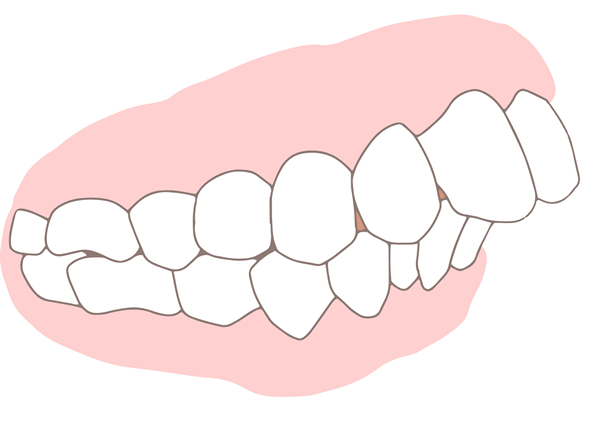

出っ歯

上の歯が前に出ているため、口を閉じるのが難しく、奥歯に大きな負担がかかります。